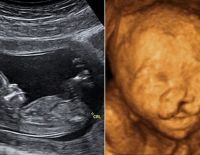

Tổng quan về kỹ thuật siêu âm 4D và những vấn đề liên quan

Siêu âm 4D là phương pháp chẩn đoán hình ảnh hiện đại, phổ biến trong lĩnh vực y học hiện nay. Kỹ thuật giúp quan sát trực tiếp các hoạt động của thai nhi, đồng thời hỗ trợ phát hiện những dị tật sớm ở...